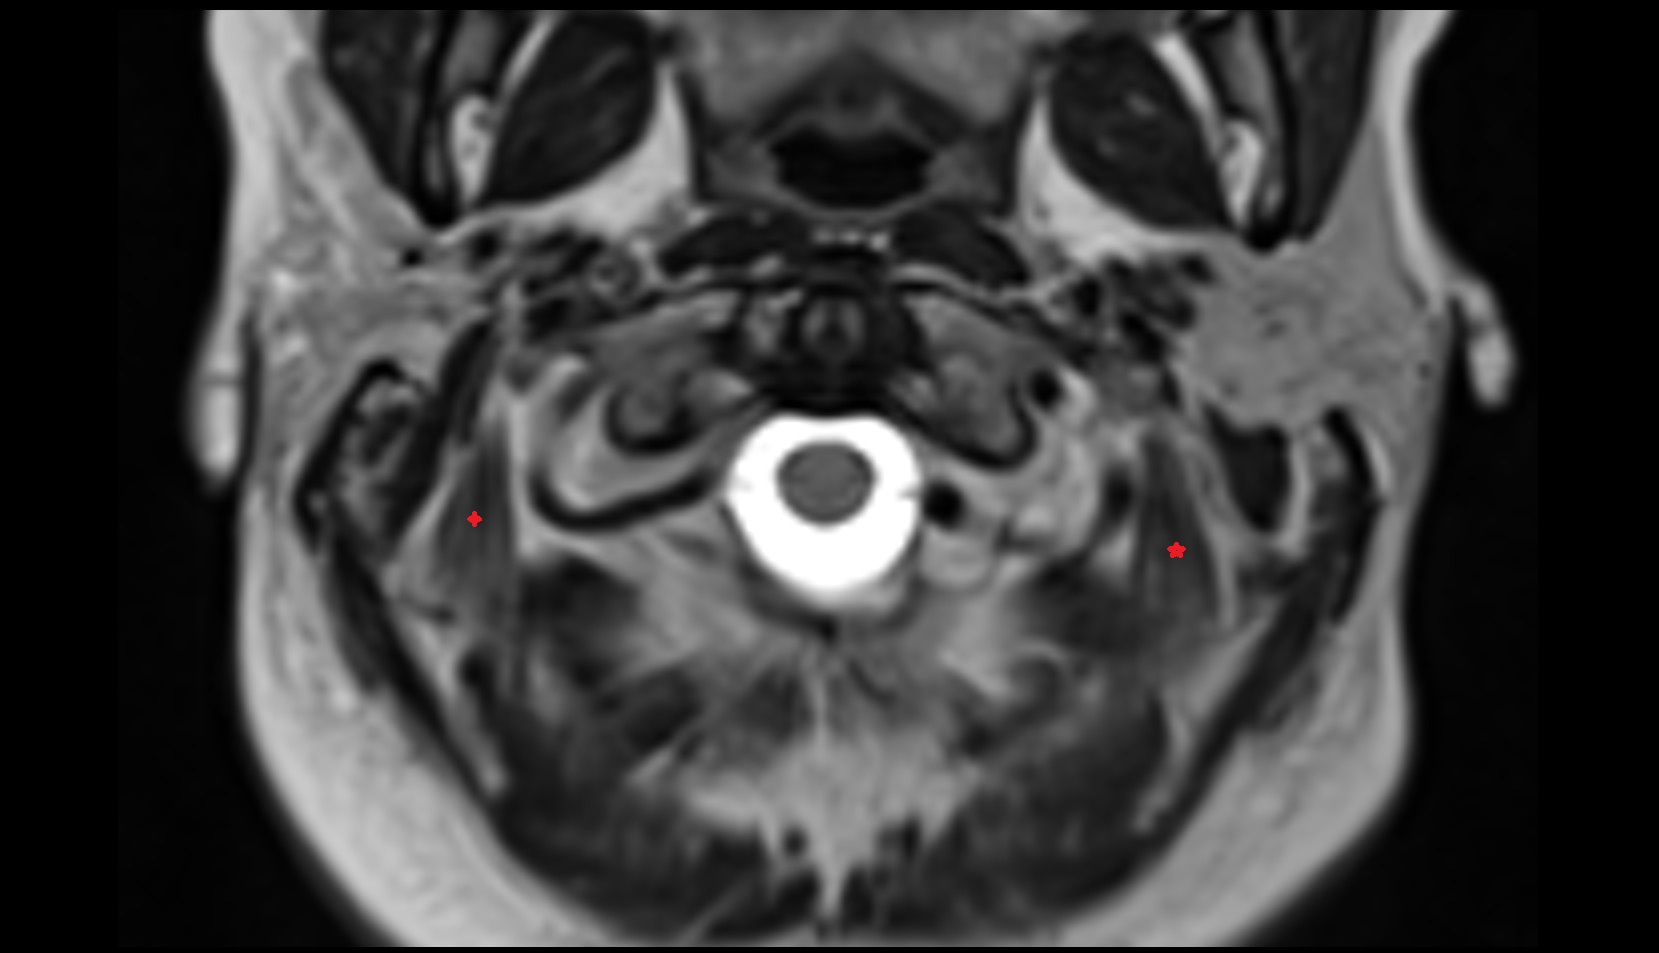

- Temporomandibular joint

- Mandibular condyle

- Mandibular fossa

- Articular disc of temporomandibular joint

- Articular eminence